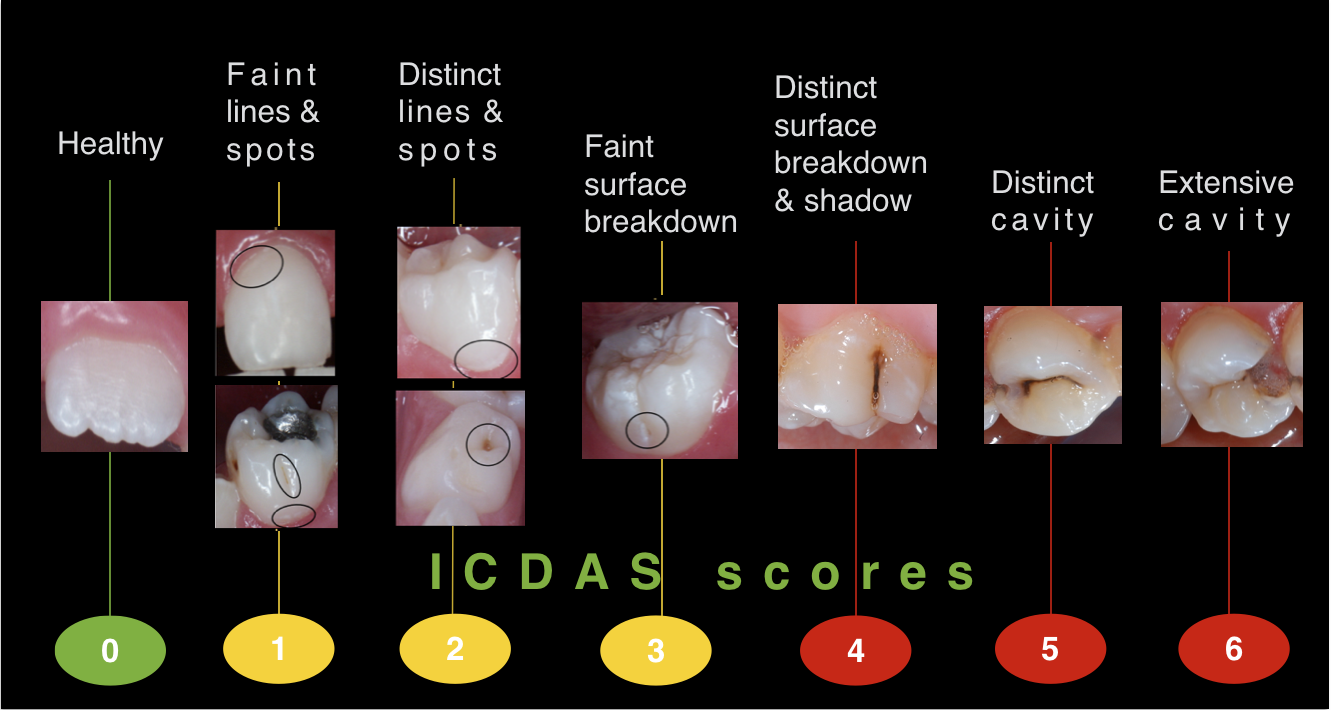

caries dental dentistry clinical diagnosis icdas management pediatric surfaces tooth lesion smooth teeth occlusal enamel criteria grading pit severity fissure